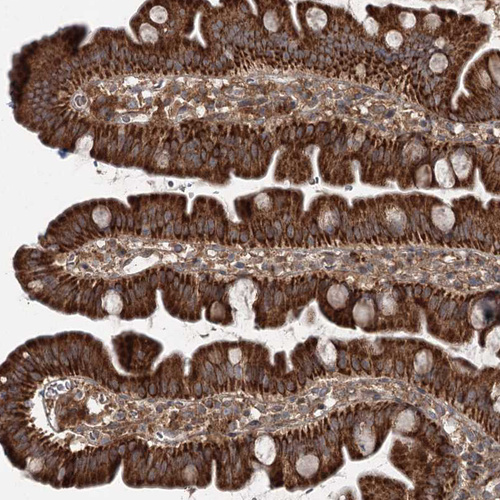

Immunohistochemical staining of human small intestine shows strong granular cytoplasmic positivity in glandular cells.